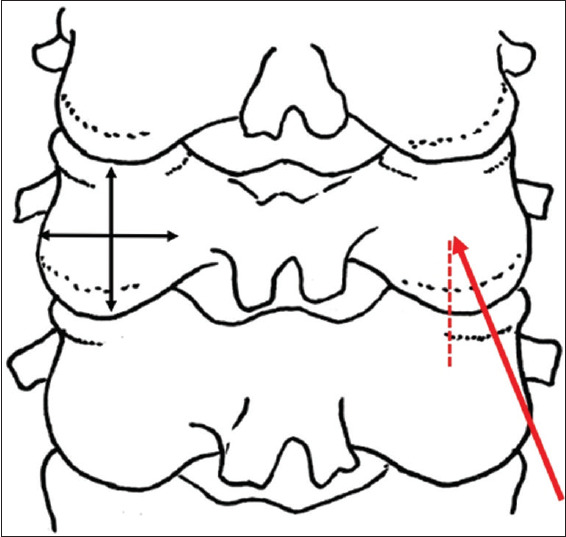

背景:侧块椎弓根内螺钉(LMIS)固定于2021年被引入,作为一种安全简单的替代方法固定下颈椎治疗各种颈椎疾病。本研究的目的是评估和比较这种新技术的螺钉拔出强度与其他两种主要方法,经椎弓根螺钉(TPS)和侧块螺钉(LMS)方法的轨迹。方法:203例在我院接受宫颈计算机断层扫描(CT)的患者纳入研究。使用从C3到C6的颈椎轴向切片选择三个轨迹中的每个感兴趣的区域,并计算CT数(Hounsfield单位)。结果:共收集4872个数据点。患者平均年龄59.5岁。男女比例为135:68。65岁以上患者93例。TPS的平均CT数为511.9,LMS为473.1,LMIS为598.5。即使对性别和年龄进行了调整,三种轨迹的CT数也有显著差异。结论:LMIS是一种有希望的替代常用方法用于下轴颈椎固定,具有显著的拔出强度。这种方法值得许多患者考虑。

Background: Lateral mass intrapedicular screw (LMIS) fixation was introduced in 2021 as a safe and simple alternative method for the fixation of the subaxial cervical spine in the treatment of various cervical spine diseases. The purpose of this study was to evaluate and compare the screw pullout strength of this new technique to the trajectories of two other major methods, the transpedicular screw (TPS) and lateral mass screw (LMS) methods.

Methods: Two hundred and three patients who underwent a cervical computed tomography (CT) scan at our institution were included in the study. A region of interest for each of the three trajectories was selected using axial slices of the cervical vertebra from C3 through C6, and the CT number (Hounsfield unit) was calculated.